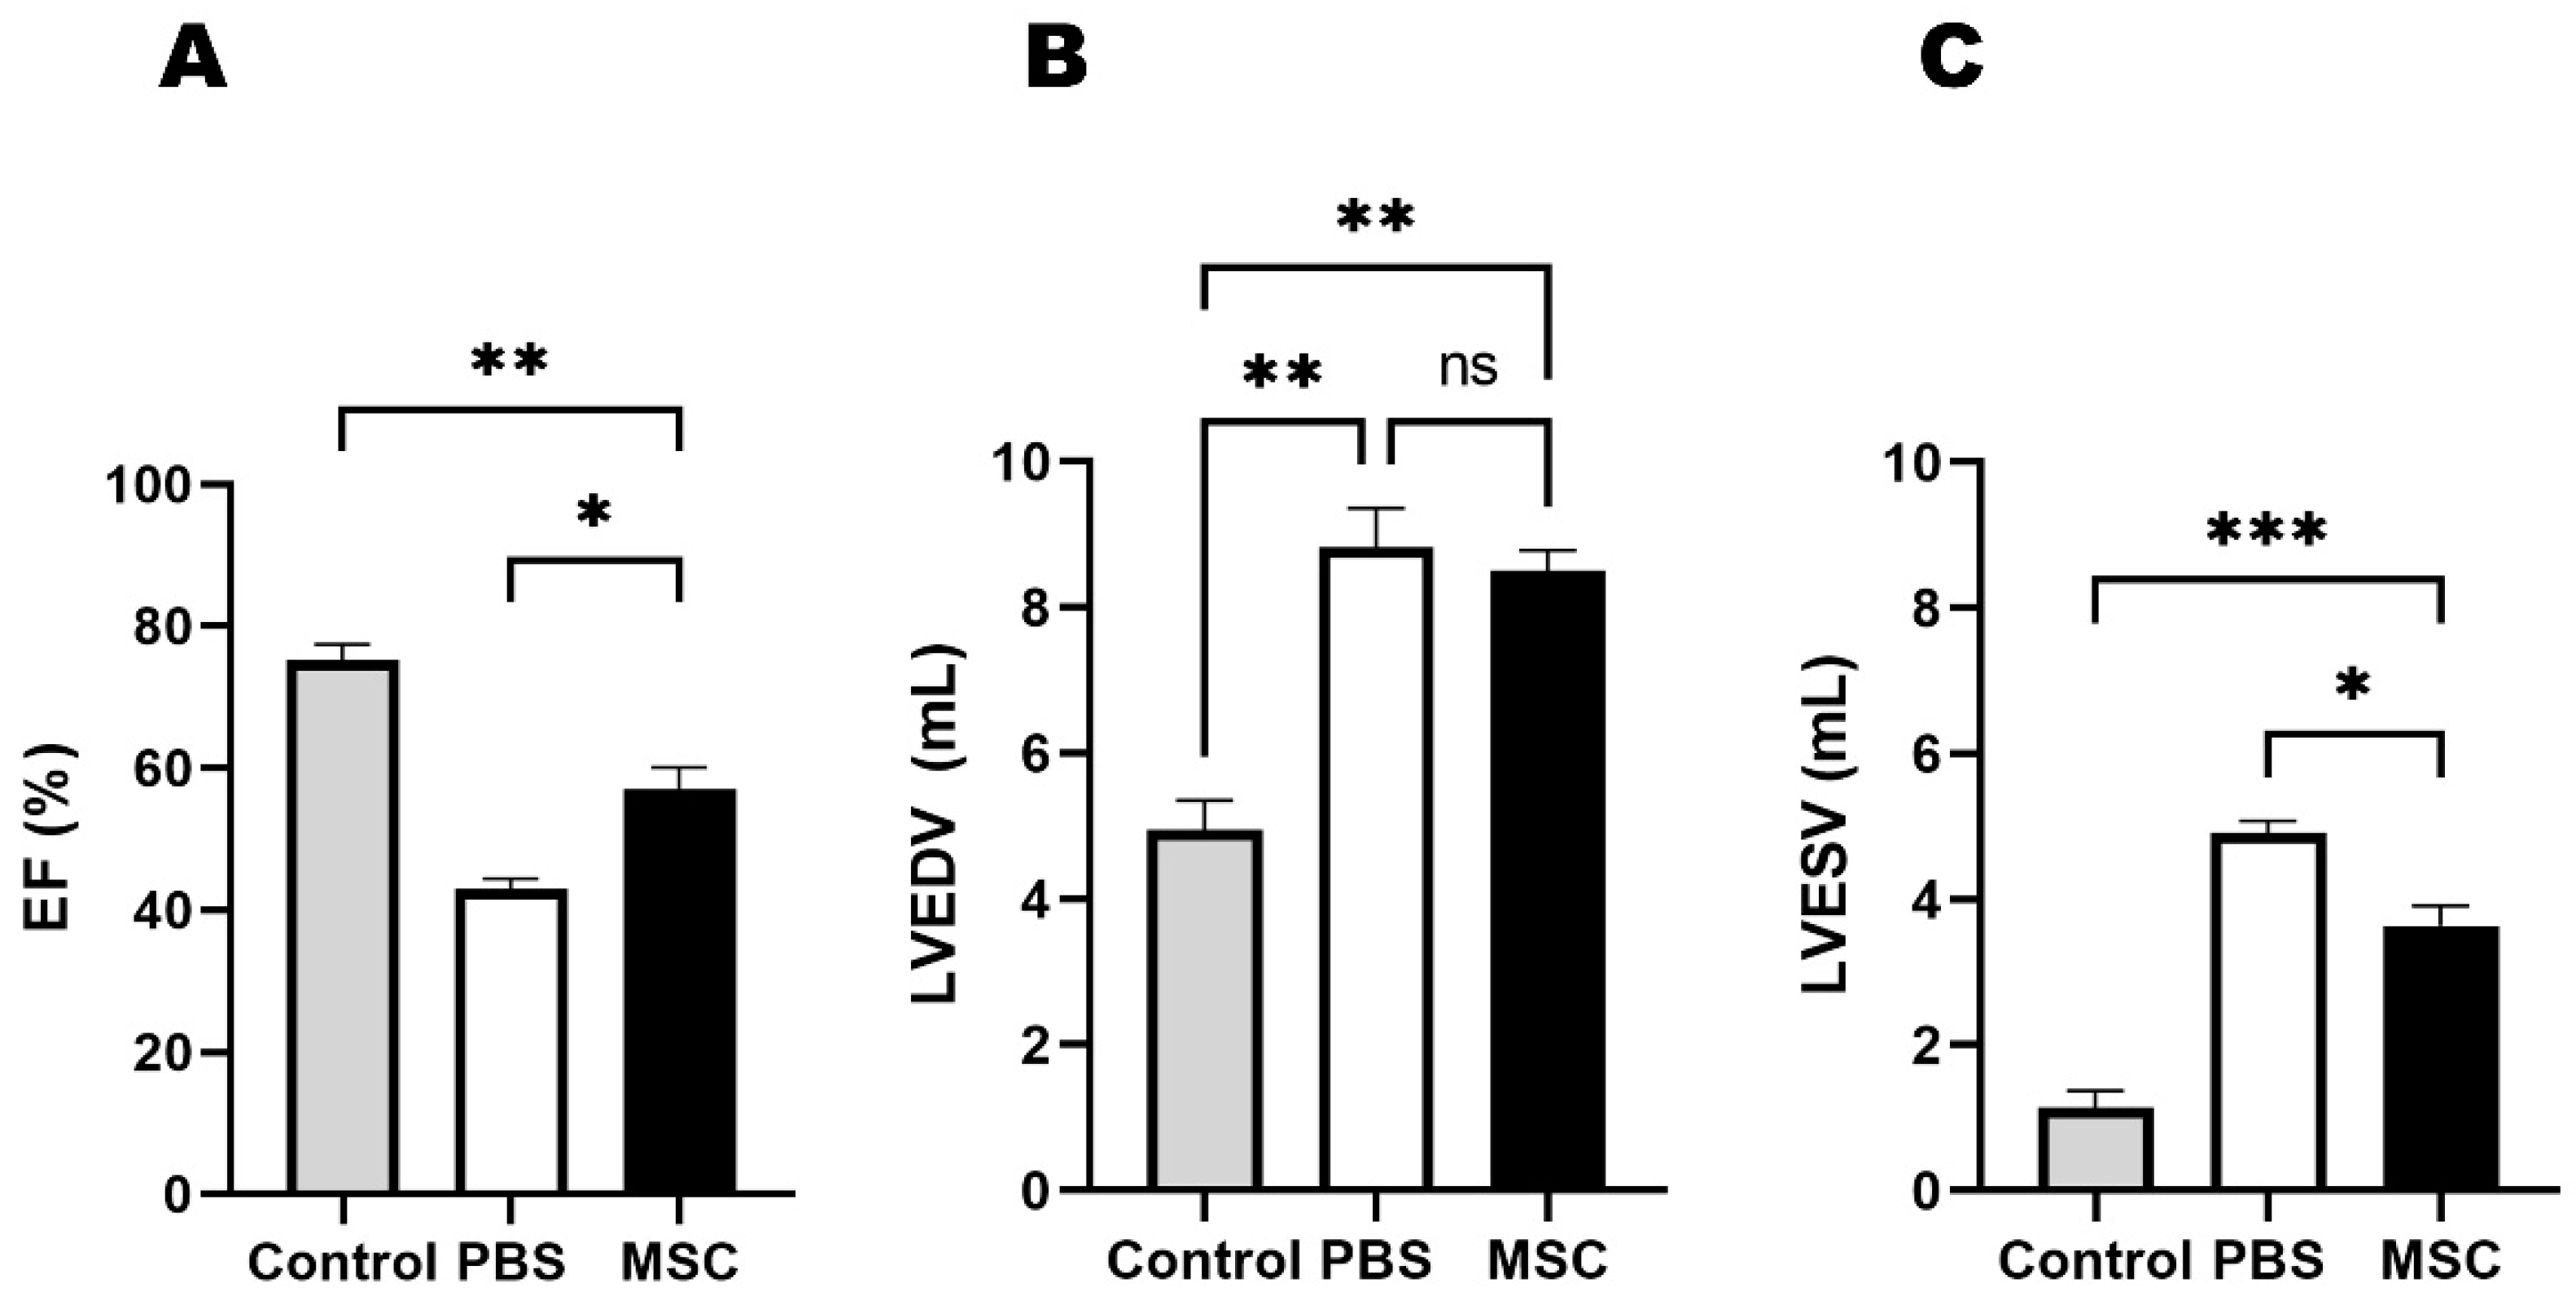

3.1. Echocardiographic Results